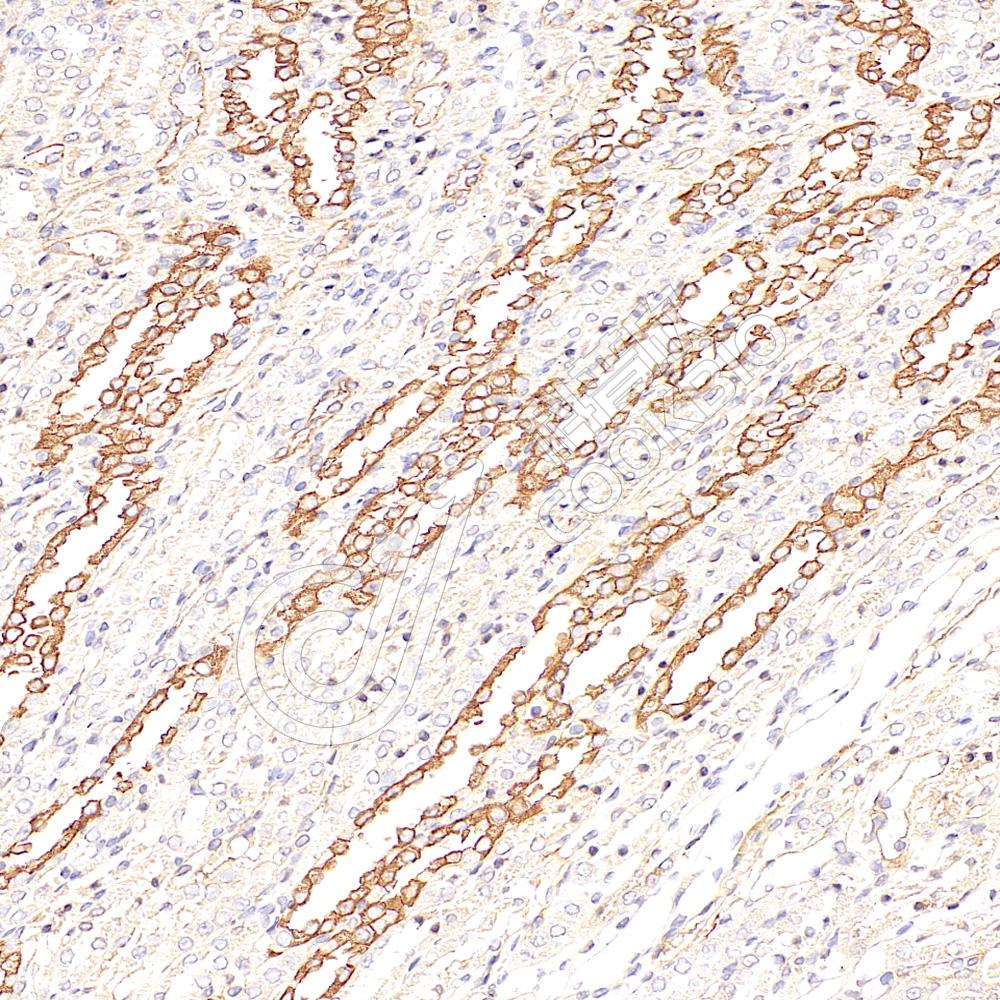

IHC检测non-muscle Myosin IIB/MYH10蛋白(货号 K2363561).

样品: 大鼠肾, 4%多聚甲醛 (货号KSG1101) 固定12-24小时.

抗原修复: 柠檬酸抗原修复液(干粉, pH 6.0) (KSG1201), 高压锅均匀喷气计时2分钟.

—抗: 1: 2300稀释, 4℃ 孵育过夜.

二抗: S-vision免疫组化多聚二抗(山羊抗小鼠), 即用型(货号KB3903), 室温孵育20分钟.